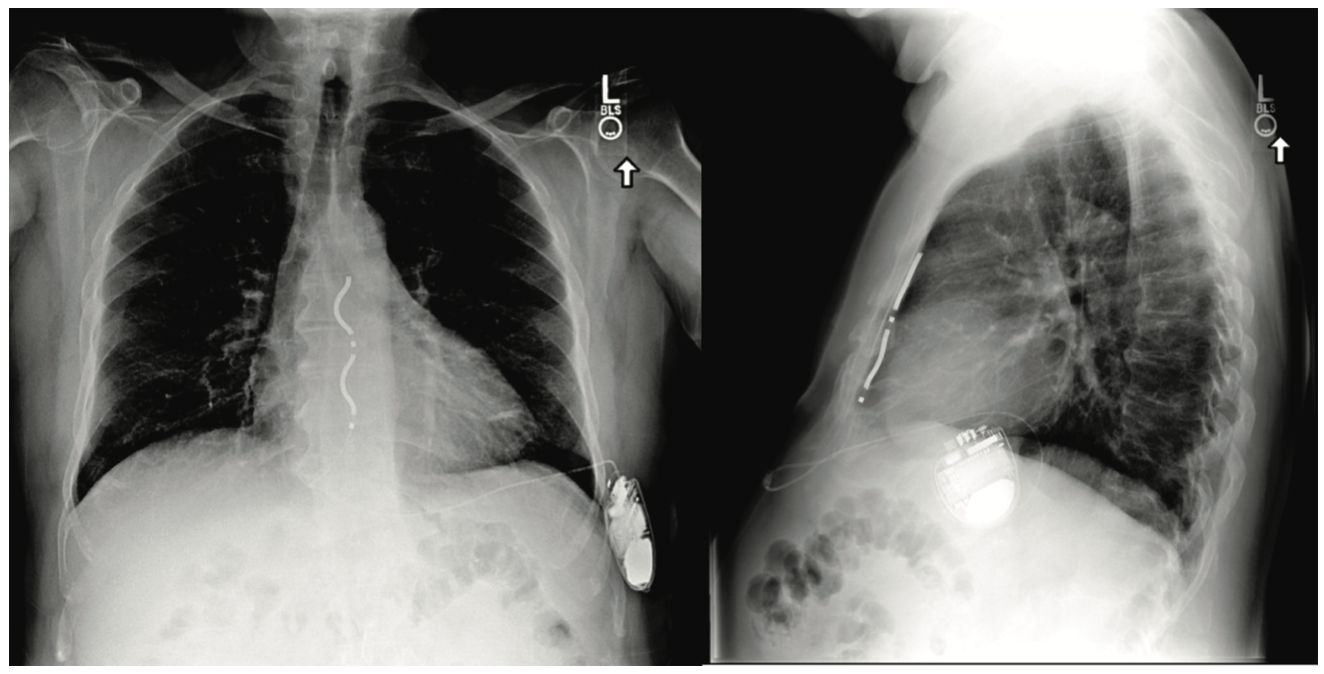

In August 2022, the results of the EV ICD Pivotal Study, sponsored by Medtronic, were presented during the European Society of Cardiology (ESC) Congress by Dr Paul Friedman and simultaneously published in the New England Journal of Medicine.3 The trial was a prospective, single-group, nonrandomized, premarket global clinical study involving patients who had an ICD indication and underwent implantation of an EV ICD system. The primary efficacy endpoint was successful defibrillation at implantation. Of the 356 patients enrolled, 316 had an implantation attempt. The procedure was performed by an electrophysiologist after hands-on training and accompanied by a cardiac surgeon during the initial implants. After surgical dissection to gain access to the substernal space, leads were implanted substernally using a tunneling tool with the use of anteroposterior (AP) and lateral fluoroscopic guidance. The lead was attached to a pulse generator that is similar to that of a transvenous ICD capable of delivering ATP and shocks of up to 40 J. The generator was implanted along the patient’s left midaxillary line. No major intraprocedural complications were reported. A postoperative chest x-ray of a patient who underwent implantation of an EV ICD system is shown in the Figure.